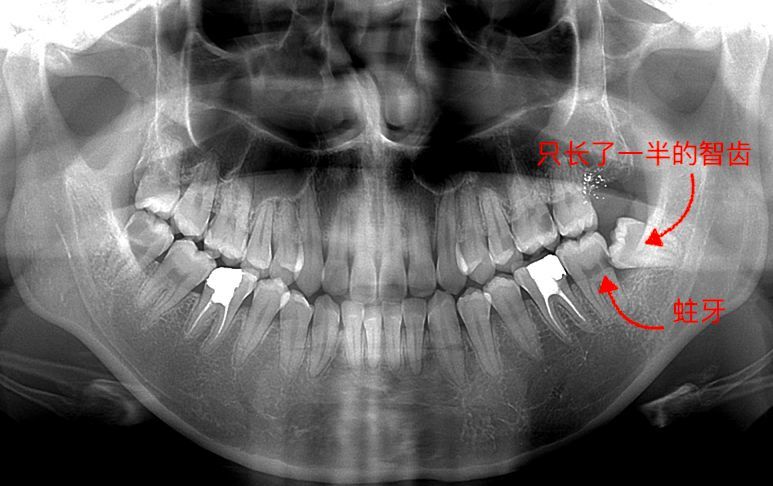

长智齿了,但是现在不疼了,去医院拍了片,请问这个智齿长这样需要拔么?

阿姨还为我们展示了两张x线片,让我们了解一下智齿的x线片,恒牙替换